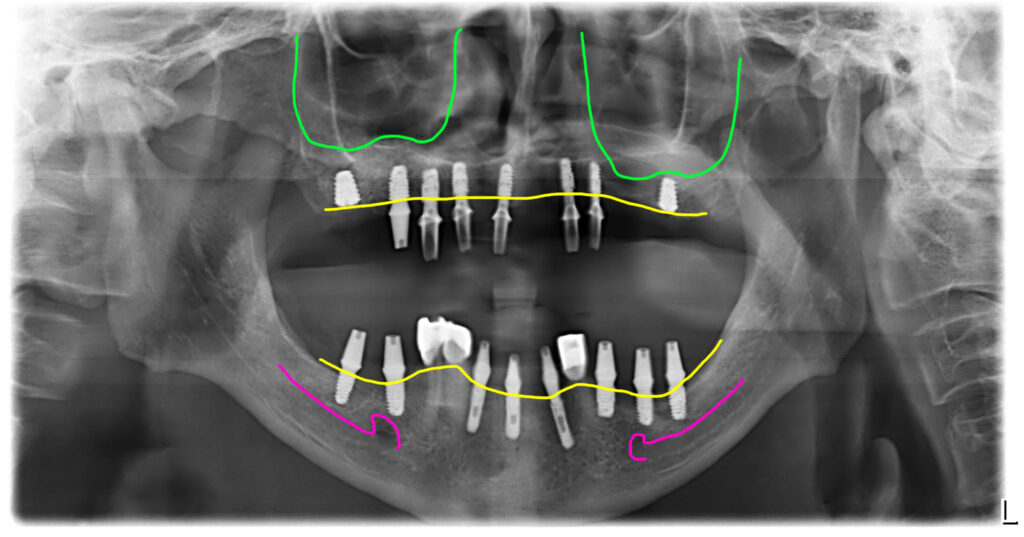

오늘 소개해 드릴 사례는 70대 남성으로 오랫동안 틀니를 사용 중이셨는데 틀니가 불편해서 임플란트로 치료한 경우입니다.

위에는 완전틀니, 아래는 부분틀니였으며 아래 부분틀니의 지대주로 사용한 3개의 치아는 치조골도 녹지 않고 튼튼해서 살리고 전체적으로 임플란트를 하기로 했습니다.

위아래 틀니를 오랫동안 사용하고 계셨던 70대 아버님이셨어요. 상악동부위에 뼈가 좀 부족했지만 뼈이식이 가능한 상태였습니다.

아래에는 부분틀니를 쓰고 계셨는데 남아있는 치아를 잘 관리하셔서 잇몸이 튼튼하고 위치도 좋았습니다. 그래서 아래 지대치로 사용중이었던 3개의 치아는 남기고 전체임플란트를 하기로 했습니다.